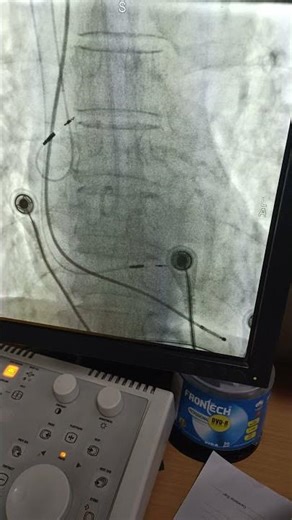

- Fluoro

Lbbb Pacing - Lead Lbba

Implant - Left Bundle Branch Pacemaker

Block - Left Bundle Pacing

Lead Placement - Left Bundle Branch Pacing Webinar